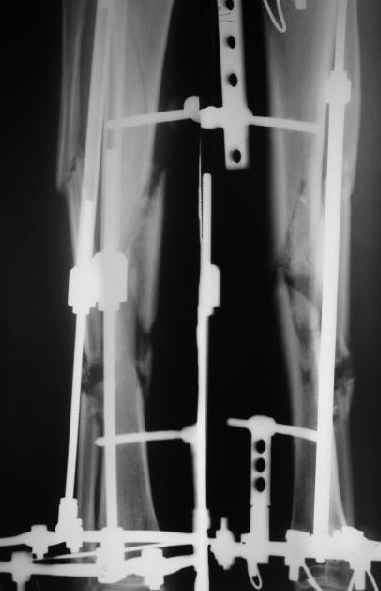

Наконец, 23 марта сделали и голень.